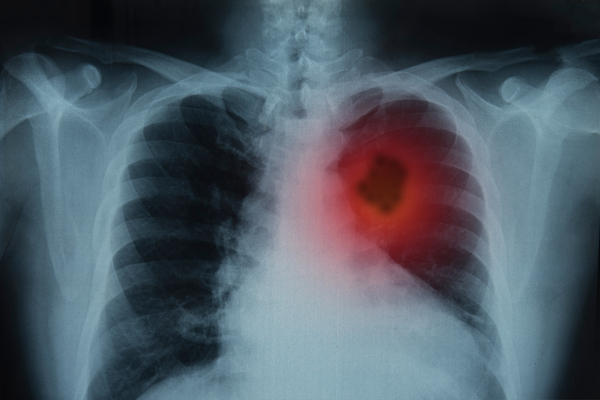

No último dia 15 de novembro, a FDA (U.S. Food and Drug Administration) aprovou o uso da substância repotrectinib para tratamento de pacientes com câncer de pulmão de células não pequenas localmente avançado ou metastático positivo para ROS1.

Fabricada pela Bristol-Myers Squibb Company, o medicamento é o primeiro que a FDA aprova para o tratamento de pacientes com câncer de pulmão de células não pequenas ROS1 positivos e que previamente já tenham sido tratados com inibidores de tirosina-quinase.